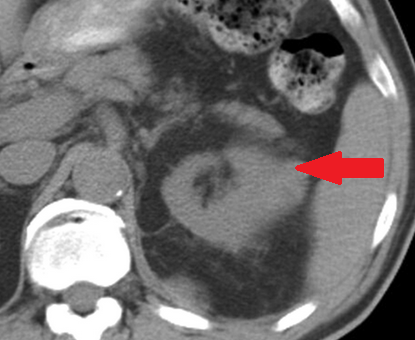

Αυτόματη ρήξη/αιμορραγία νεφρού — νεφροκυτταρικό καρκίνωμα (Ευγενική παραχώρηση Dr. V. Penopoulos)